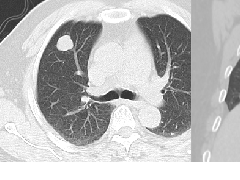

3、CT平扫表现一个或多个肾锥体内散在或蔟团状多发结石,呈花瓣样或扇形分布;部分腹部平片阴性,CT平扫可发现肾锥体内细小的结石。增强扫描表现扩张的肾集合管内有条纹状、刷状、小囊状或扇形的造影剂浓聚。部分患者肾实质内可见多发小囊肿。